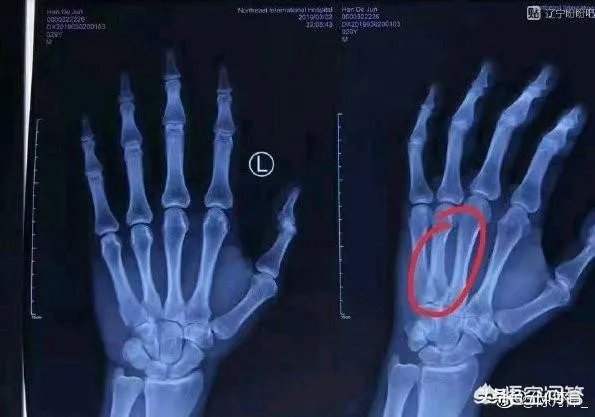

3月4日据消息透露,韩德君今日在北京积水潭医院对伤手再次进行了诊断,并最终敲定了治疗方案。据消息称,韩德君对骨折的手掌进行了石膏外固定,他的伤手需要6周时间恢复。

在去医院治疗中,获悉治愈需要6周,手指对于一个篮球远动员。尤其是靠抢篮板得分的韩德君来说不得不说是个沉重的打击,而这个时间点居然是在半决赛。

韩德君在与广厦的比赛中由于扣篮用力过猛,致使手掌骨折,据最新消息,大韩的伤病采取保守治疗,估计半决赛时可以复出。众所众知,韩德君在辽宁阵中是非常关键的一环。